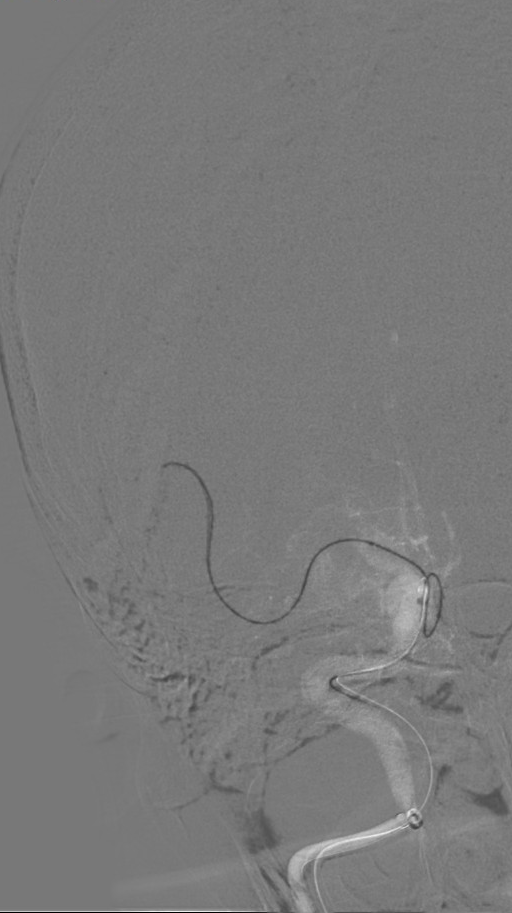

造影评估:

2.0×15mm球囊加压时可见“腰”,加压至8ATM维持5min。

扩张后造影见血流改善,支架内未见明显血栓影。

观察10分钟回收支架后,继续观察15分钟提示血流良好。

从完成穿刺到血管开通总用时仅40分钟。